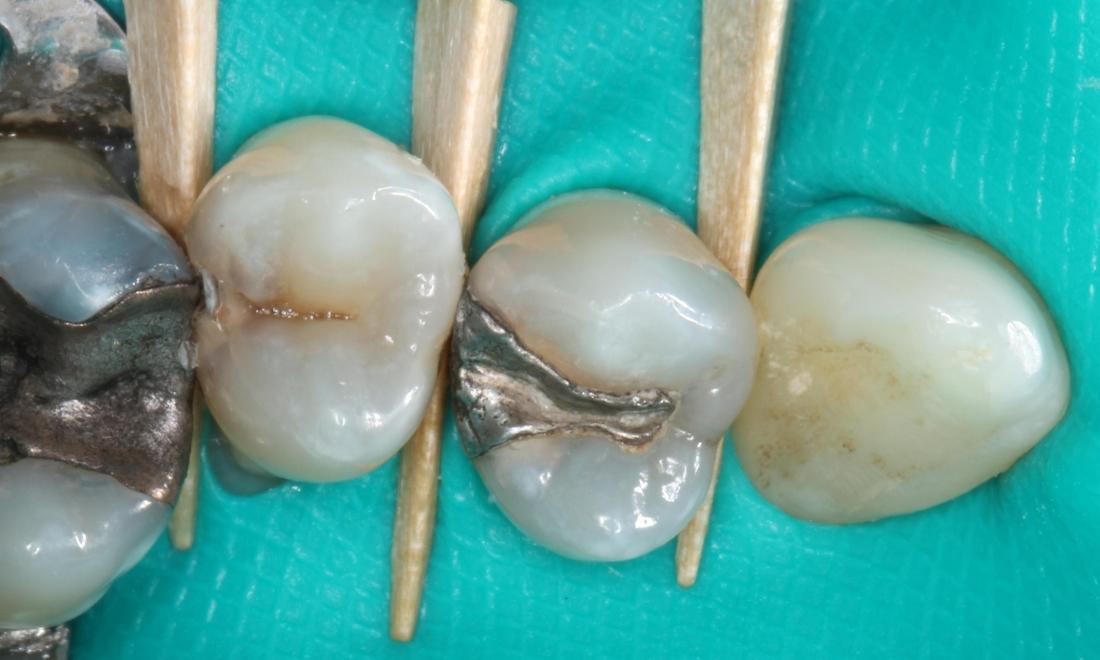

Sensitivity to hot, cold, and sweet can all be signs of a tooth decay. The decay could be under an existing filling or crown, or it could be a new cavity between two teeth. This patient one new cavity that had grown to the point of trapping food between the teeth. They also had decay forming under an existing silver filling.

We used a rubber dam to protect the lips, cheeks, gums, and prevent the patient from swallowing dental tools. Wedges were used to separate the teeth and further protect the gum tissue.

Then we removed the decay and existing filling. The decay and silver caused stain to the inside of the teeth. The teeth were then disinfected and restored to normal color and function with direct composite resin.